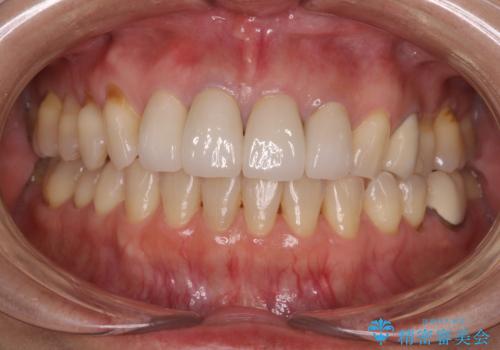

左右対称で明るく自然な前歯に仕上げることができました。